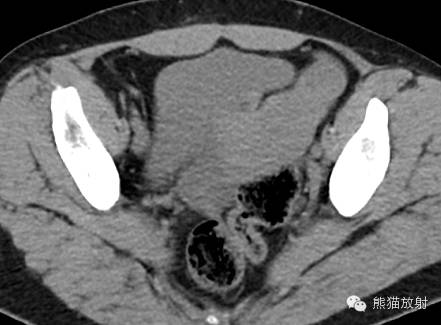

女,33岁,2年余前在月经期时,出现尿频、尿急,伴全程肉眼血尿,呈淡红色,无血块,有时可有尿痛;经期结束后,上述症状消失。

膀胱镜检查:膀胱三角区及各壁粘膜可见充血炎性改变,三角区后方可见一范围约1.5×2cm的粘膜隆起,局部可见紫蓝色的粘膜下瘀斑,于该处取病理2;

活检病理示:(膀胱)送检少许组织被覆尿路上皮,呈轻度慢性炎,间质中查见少数散在的腺体,结合临床和免疫表型,符合子宫内膜异位;免疫组化:ER 、PR 、CD10-、CK34βE12±、CK7±。

诸病灶分别如下图中圆圈所示: